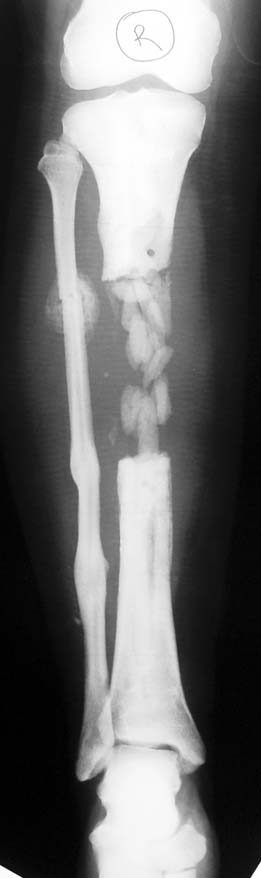

Chronic osteomyelitis leads to necrosis of bone and soft tissues. Dead bone is a nidus which hosts pathogenous microorganisms. Defence mechanisms of the host is usually not in optimum condition to deal with microorganisms. Antibiotics can’t reach the infection site because blood flow is disrupted. For these reasons, dead bone has to be completely removed by radical debridement.

Appropriate radical debridement necessitates excision of all necrotic bone and soft tissues, and frequently causes instability at the involved extremity. The remaining bone and soft tissue defect has to be fixed and reconstructed. The distraction osteogenesis method of Ilizarov is used successfully for achievement of union, correction of the deformity, elimination of limb length inequality and reconstruction of segmental bone defects.